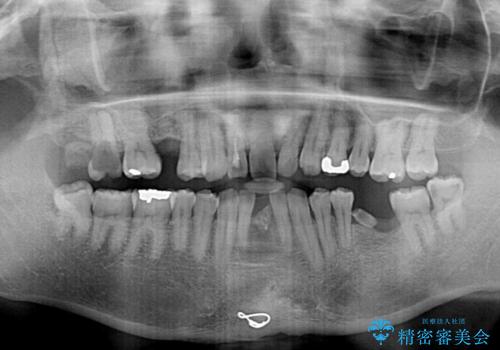

- むし歯治療途中で放置された歯が多く、スペースができたり歯が寄って来たりしているのを気にして来院された患者様です。

矯正治療を行いながら、欠損部はインプラントによる補綴治療を希望されたため、補助装置を用いたワイヤー矯正によりスペースを確保しながら歯列を整え、適宜インプラントを埋入していくこととしました。

上顎前歯もインプラントを希望していらっしゃいましたが、両隣の歯根が近接しており、インプラントは困難と判断したためオールセラミックブリッジによる補綴治療を前提として治療を開始することとしました。

在宅勤務のため、前歯にスペースが長期間できることに対して特に問題はないとおっしゃったため、スペースはそのままに治療を進めていくこととしました。